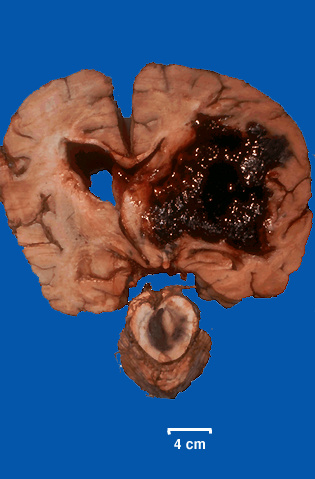

This is a coronal section of the brain and midbrain at autopsy. [Image contributed by Jeannette J. Townsend, MD, University of Utah]